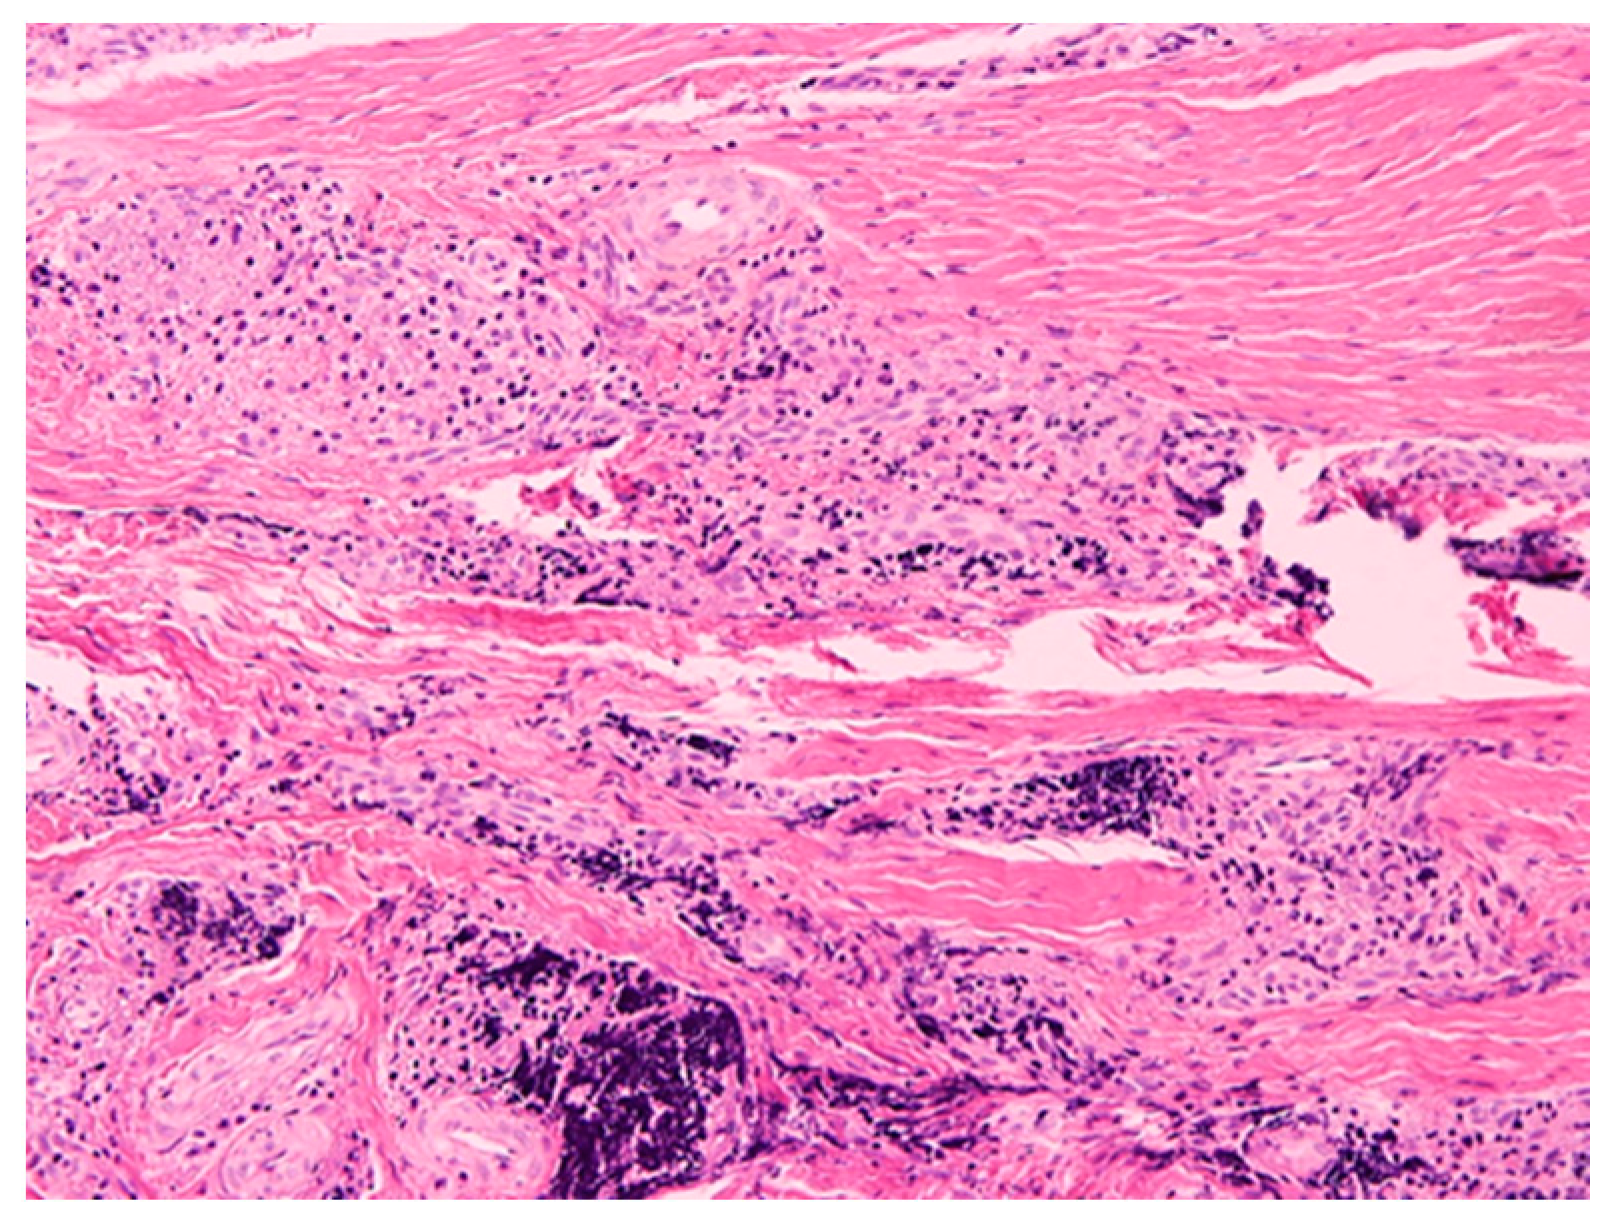

4.3. Histopathological Examination